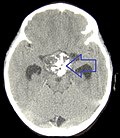

Imaging

Radiology:[1]

- Calcifications (adamantinous type).

- Contrast enhancing.

- Cystic portions.